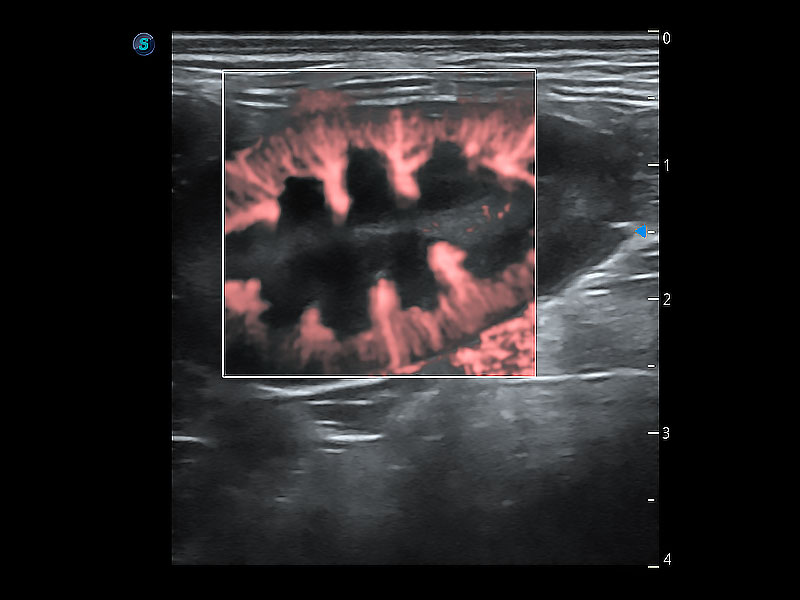

• Micro F 显微血流成像

极大提升超低速微细血流的检出能力,同时更精准地滤除软组织和超声信号,为兽用医生提供以往无法通过常规血流获得的疾病诊断信息。

• Bright Flow 立体血流成像

在传统二维血流成像的基础上,呈现血流的立体感,具有动感的生命力之美。即便是微小的血管也能轻松应对,提高了血流的视觉敏感性。

(犬)肾脏显微血流